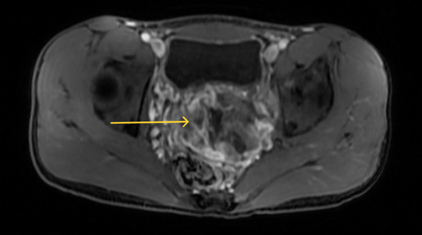

- Chụp MRI ổ bụng có tiêm thuốc đối quang từ: Có hình ảnh khối vùng tiểu khung kích thước 64x99mm, tăng tín hiệu trên T2W, hạn chế khuếch tán, ngấm thuốc sau tiêm, phần trung tâm hóa dịch không ngấm thuốc sau tiêm, tổn thương xâm lấn niệu quản trái đoạn 1/2 dưới gây giãn niệu quản phía trên.

Hình 1: Hình ảnh MRI ổ bụng có khối ở vùng tiểu khung, tăng tín hiệu trên T2W (mũi tên vàng)